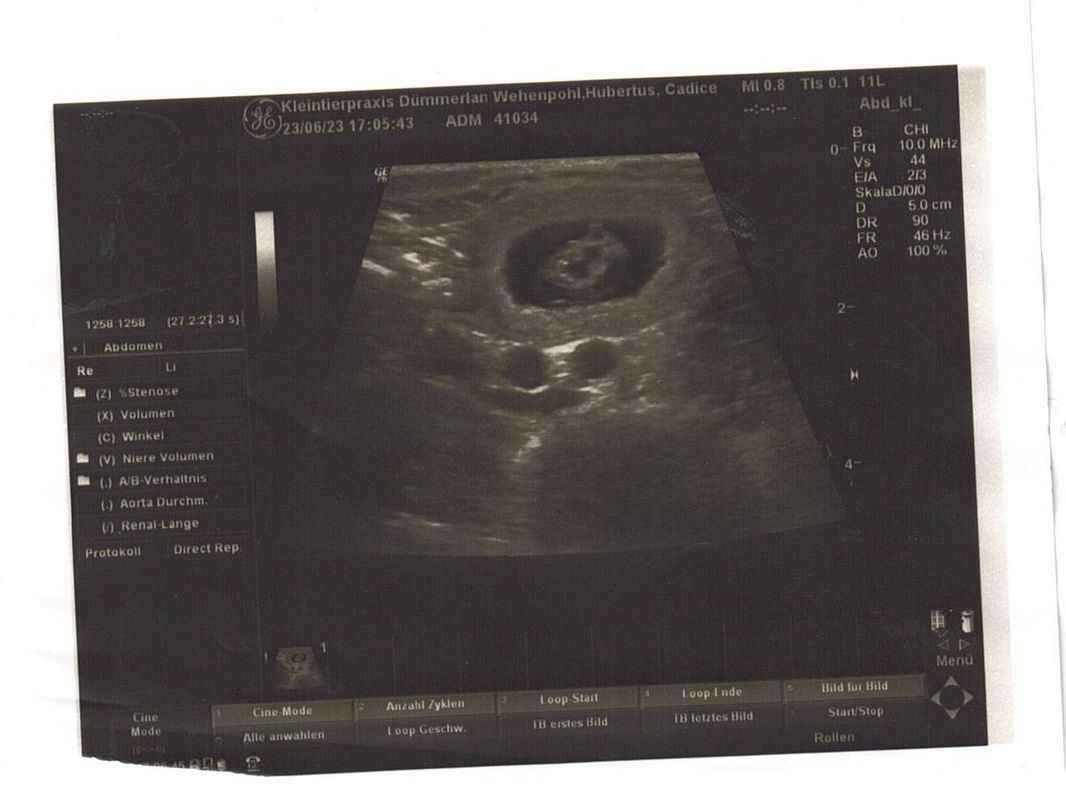

23.06.2023 Tag 26

Heute waren wir beim Ultraschall und konnten auf den ersten Blick 3 Fruchtanlagen sehen. Das heißt wir erwarten nun 3+ Welpen, wieviele es wirklich werden, zeigt sich Ende Juli.

Bauchumfang: 54 cm (+6 cm)